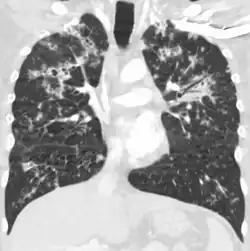

A case of miliary tuberculosis in an 82-year-old woman:

-

X-ray, 13 days after onset, showing bilateral interstitial infiltrates -

CT, 16 days after onset, showing extensive pulmonary parenchymal involvement consisting of irregular septal thickenings with ground-glass areas and centrilobular nodules with a peri-lymphatic distribution -

X-ray, 22 days after onset, showing extensive bilateral reticulo-nodular infiltrates -